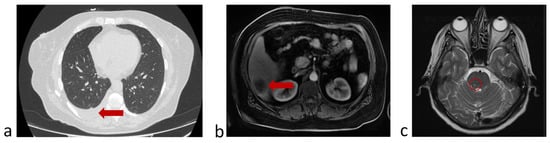

3.6.2. A Clinical Example Demonstrating a Unfavorable Outcome of the Disease and the Evolution of the Number of CTCs Detected in the Peripheral Blood